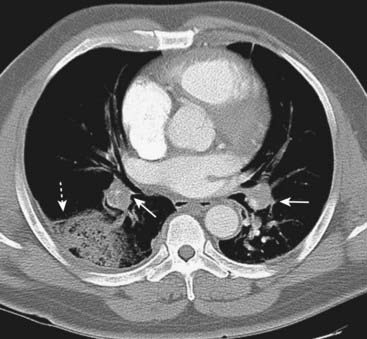

Figure 12-21 Saddle and peripheral pulmonary emboli.

Acute pulmonary emboli appear as partial or complete filling defects centrally located within the contrast-enhanced lumina of the pulmonary arteries. A, A large pulmonary embolus almost completely fills both the left and right pulmonary arteries (solid white and black arrows). This is a saddle embolus. B, A small, central filling defect is seen in a more peripheral pulmonary artery (dotted white arrow). This pulmonary artery seems to be floating disconnected in the lung because the plane of this particular image does not display its connection to the left pulmonary artery.